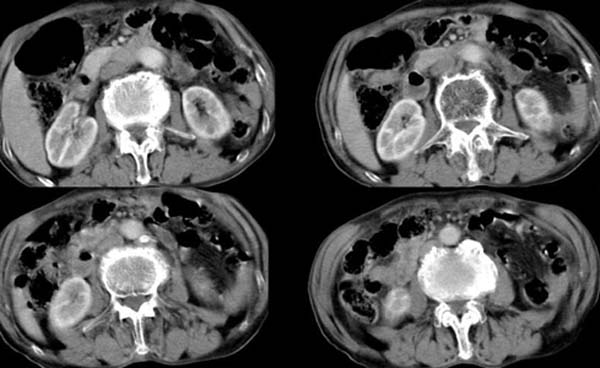

以下是引用zsl6918在2008-4-12 22:27:00的发言:[br]肝内未见异常密度灶,脾脏大小如常,腹主动脉旁可见一肿大淋巴结影,密度均匀,未见明显坏死表现。腹腔干被包绕,但未见明显侵犯,胃腔充盈尚可,未见明显占位表现。胰腺显示良好,略示前方移位。考虑腹膜后淋巴瘤可能性大。依据,转移瘤多有坏死表现,且有恶性肿瘤病史。第二,淋巴瘤未经治疗很少出现坏死表现,此点符合。第三,腹膜后其他肿瘤已经发现一般较大,本病例结节大小符合肿大淋巴结的表现。故首先考虑淋巴瘤。建议临床进一步检查其他部位的情况,另外结合实验室检查,注意病人有无贫血及低热表现。